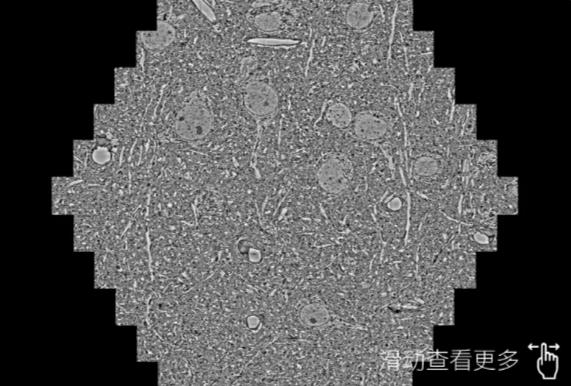

鼠脑切片。左图使用琼海蔡司琼海扫描电镜MultiSEM706对165μmx143pm面积区域成像,耗时仅需1.5秒。右图为鼠脑切片中30μm区域放大效果。样品由芝加哥大学B.Kasthuri提供。

使用蔡司高速琼海扫描电镜MultiSEM对1mm²人脑皮层组织进行高分辨成像,并对其中的各种细胞结构进行三维重构分析。左图展示了2x3mm²组织平面中锥体神经元的三维重构效果。右图显示了局部体积神经元三维重构。图像由哈佛大学chtman实验室提供,渲染图由D. Berger 制作。